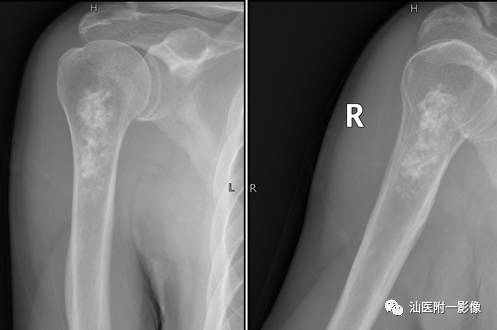

•好发于长骨的干骺端(膝关节周围、肱骨近端)。

•软骨母细胞瘤为来源于幼稚软骨细胞(软骨母细胞)。

•常见于青少年,多发生于10~20岁之间。

•多发生于四肢长骨,以胫骨、股骨和肱骨多见。

•软骨母细胞瘤的溶骨区常常开始位于骨骺,倾向于越过骨骺线,向干骺端蔓延。